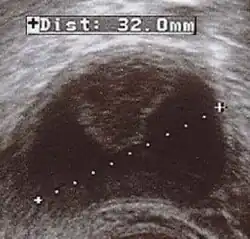

| Corpus luteum cyst with bleeding. Fresh blood is anechoic (black). A protrusion of coagulated blood (lighter in color) can also be seen in the top of the cyst. | |

In women of reproductive age, cysts with a diameter of less than 5 cm (2.0 in) are common, clinically inconsequential, and almost always a physiological condition rather than cancer or another medical condition.[3] In postmenopausal women the threshold for concern is 1 cm (0.39 in).[3] Although ovarian cancer may be cystic, it does not arise from benign corpus luteum cysts.[3] Medical specialty professional organizations recommend no follow-up imaging for cysts which are considered clinically inconsequential.[3]